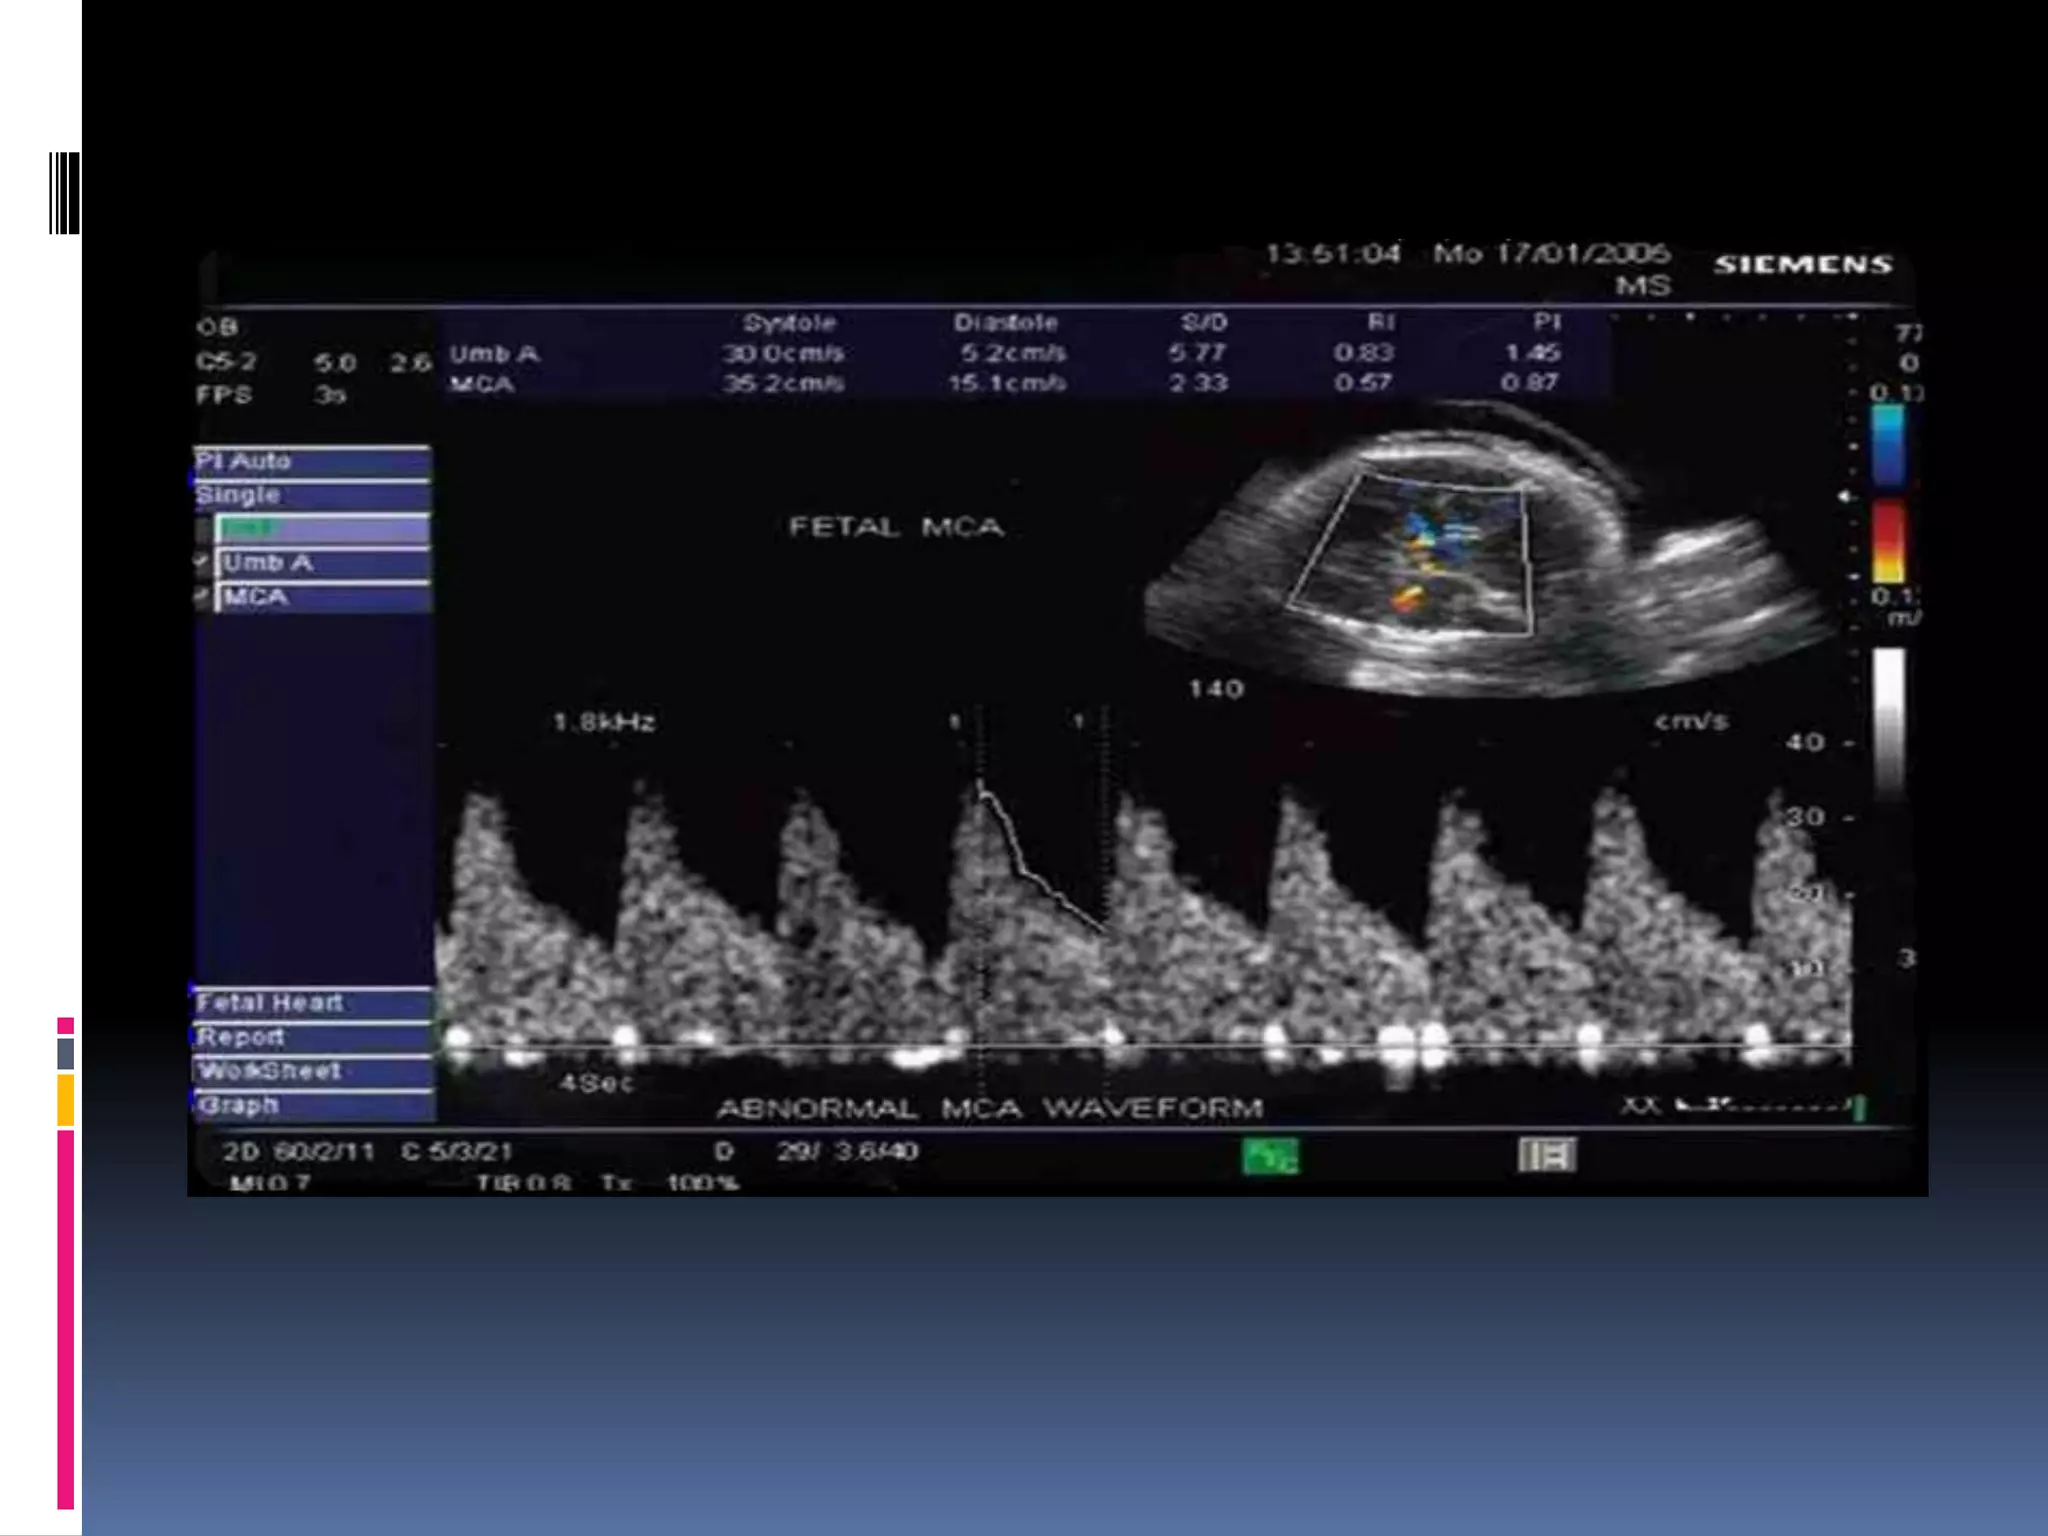

Fetal side; Middle cerebral

circulation

The cerebral circulation is normally a high

impedance circulation with continuous

forward

flow throughout the cardiac cycle.

The middle cerebral artery is the most

accessible

cerebral vessel to ultrasound imaging in the

fetus,

and it carries more than 80% of cerebral blood

flow.

In the presence of fetal hypoxemia, central

redistribution of blood flow occurs, resulting in an

increased blood flow to the brain, heart, and

adrenals, and a reduction in flow to the

peripheral and placental circulations.

This blood flow redistribution is known as the

brain-sparing reflex, and plays a major role in

fetal adaptation to oxygen deprivation.

34 weeks viable fetus with normal umbilical artery blood flow.

 In the hypoxic fetus, the cerebral vasculature dilates

and this causes a reduction in the MCA pulsatility

index in a phenomenon known as “brain sparing”.

With disease progression the fetus is no longer able to

compensate, and resistance in the MCA increases.

 In the preterm (<32 weeks) small for gestational age

fetus, MCA Doppler has limited accuracy in predicting

acidaemia in the absence of other Doppler

abnormalities.

 In the term small for gestational age fetus with

normal umbilical artery Doppler, an abnormal MCA

Doppler (PI < 5th centile) has moderate predictive

value for acidosis at birth and should be used to time

delivery.